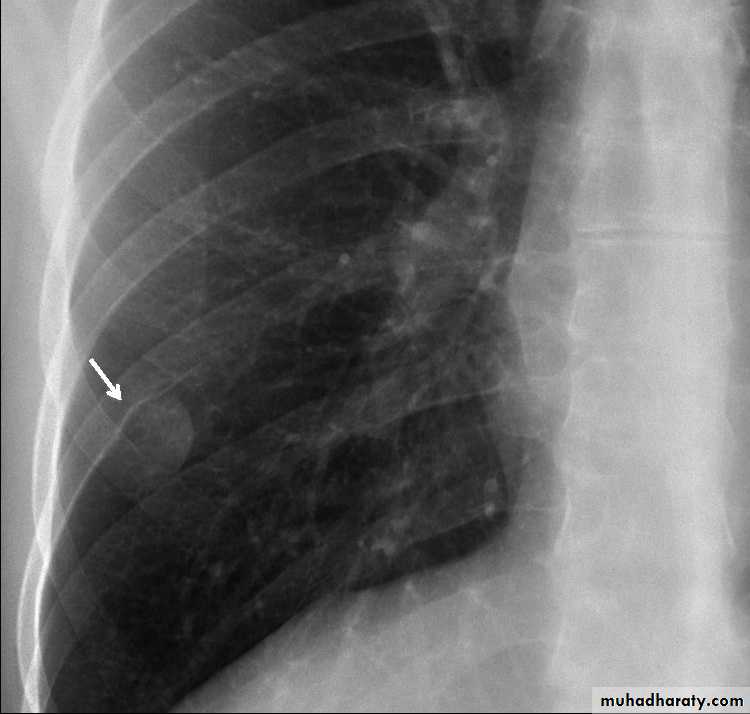

Patient with fever, rigor and dyspnea